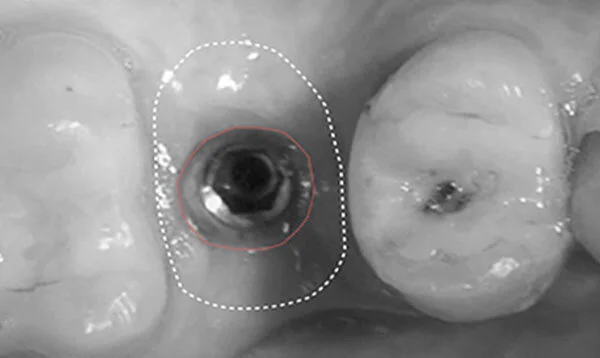

The CERVICO system includes two simple work blocks that offer a quick, easy and convenient solution in implantology for creating an excellent emergence profile and the correct implant position.

The CERVICO system helps to achieve an ideal profile with each implant case.

“The Cervico SystemTM was developed after experiencing numerous problems in my large and busy referral based implant clinic in Greece. I am sure you have experienced the same frustrations with patients who complain of food impaction and malodor around implant crowns, peri-implantitis associated with cement sepsis, concern of open contact between the implant crowns and the adjacent teeth, the unscrewing of the prosthesis or abutment, the de-cementation of the prosthesis and finally unfulfilled aesthetic results.

I knew I could not provide my patients or referring dentists with the highest level of care and the most natural final result if I did not find the answer to this industry wide problem.”

Ioannis Vergoullis DDS, MS

CERVICO founder